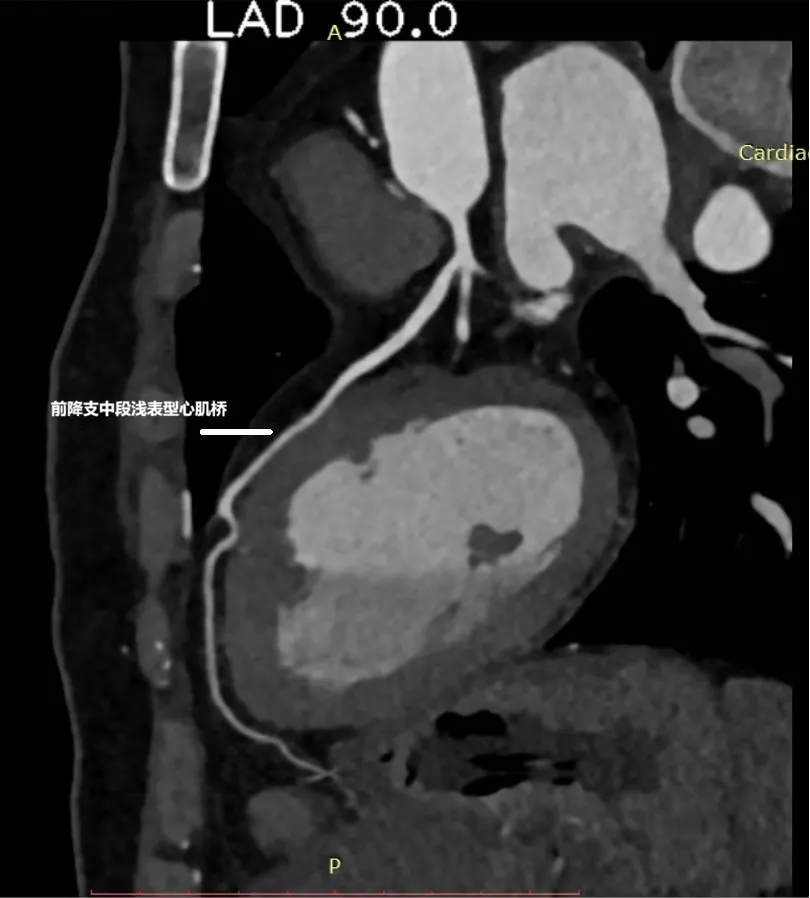

图 | 冠脉CTA图像3:前降支中段浅表型心肌桥

这还不是最终答案。为了看得更清楚,李医生建议张先生住院接受冠状动脉导管造影——这是诊断冠脉问题的“金标准”。

“我们发现,问题主要出在那个心肌桥上。”李医生指着影像解释道,“CT上看到的心肌桥,在造影下原形毕露。在心脏收缩时,这段覆盖在血管上的心肌会像承受“紧箍咒”一样,用力挤压下面的血管,压迫程度最高时甚至达到了90%!”

这就能解释为什么常规检查会“失灵”了。心电图捕捉的是静态或负荷状态下的心电信号,普通CT也难以观察到动态的血管压迫。而李延林医生通过层层递进的精准检查,终于找到了那个在“动态”下才暴露出来的“元凶”——因严重心肌桥压迫导致的心肌缺血,进而诱发了晕厥。